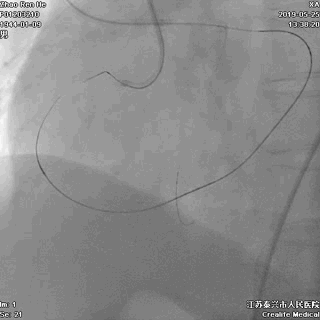

逆向途径开通RCA